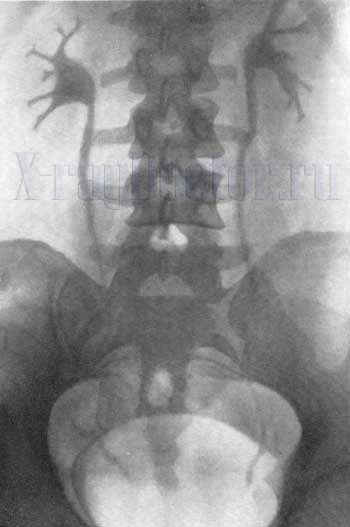

Внутривенная (вв) урография проводится с контрастом (урографином или омнипаком), введенным в локтевую вену. Контрастное вещество выводится из организма через мочевыделительную систему, поэтому «засвечивает» анатомические структуры.

- первый снимок выполняется на 7-й минуте после введения контраста;

- второй – на 15-й минуте;

- третий – на 21-й минуте.

Такая экспозиция необходима, чтобы проследить экскреторную (мочевыделительную) функцию почек. Физиологически мочевыделительная система должна через 30 минут полностью элиминировать вещество в мочевой пузырь.

На 7-й минуте контраст только попадает в лоханку. На 15-й минуте достигается тугое наполнение лоханок и уретры, что позволяет проследить состояние чашечек лоханок, ход и положение мочеиспускательного канала. Получается прекрасный контрастный снимок, который легко читать рентгенологу. На нем видна не только анатомическая структура, но и движение урографина.

На 21-й минуте рентгенография почек отражает состояние мочевого пузыря.